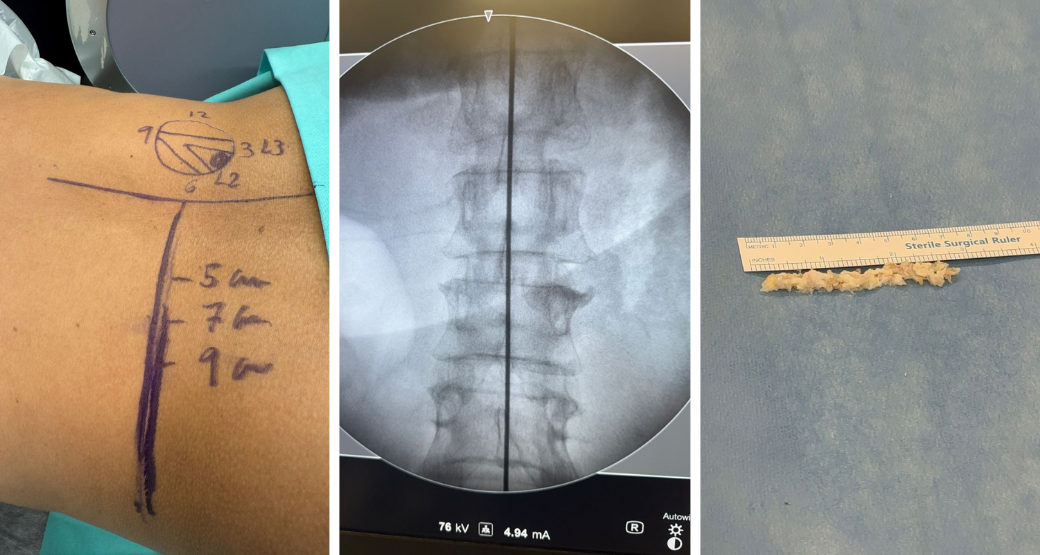

Cirurgia endoscópica extra-foraminal em 22.10 às 17h

“Após posicionamento adequado da paciente e controle radiológico, introduzimos o endoscópio, lateralmente, sem necessidade de ressecção óssea ou operação do processo articular” descrevem os cirurgiões especialistas no procedimento.

Através da via lateral do forame foi possível visualizarem, diretamente, o fragmento discal herniado, o qual foi cuidadosamente removido sob visão endoscópica.

“Durante o procedimento, liberamos completamente a raiz L2, com pulsação livre e sem evidência de compressão residual”.

Durante o ato operatório que durou cerca de 30 a 40 minutos não houve intercorrências. Hemostasia (mecanismo que evita a perda excessiva de sangue e previne infecções) adequada e preservação integral das estruturas ósseas e ligamentares.